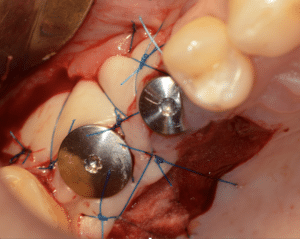

Fig.7 : Mise en place de la vis de cicatrisation. Le greffon est enfoui en vestibulaire.

Visualisation du site donneur. Technique de prélèvement à une incision.

Fig.8 : Contrôle postopératoire à 10 jours.